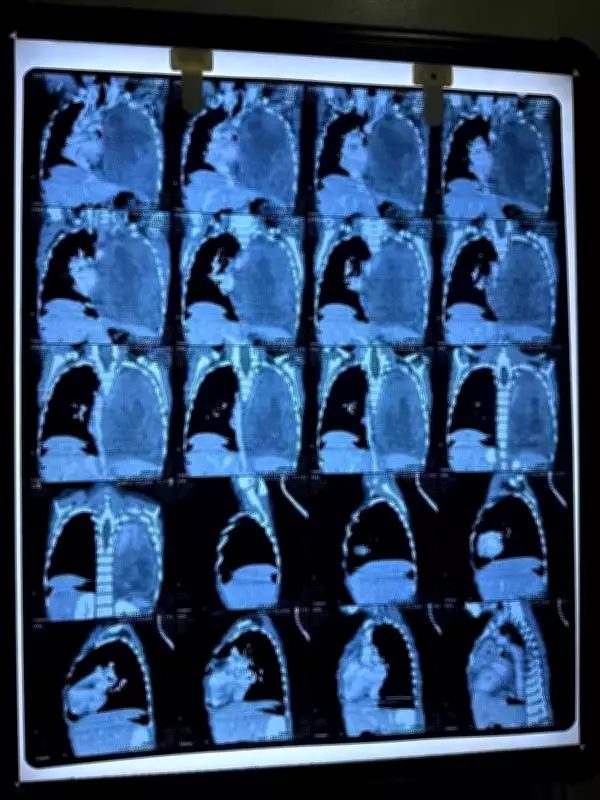

In January 2025, a CT scan unveiled a massive 11x10 cm tumor located in her left chest cavity. A follow-up contrast-enhanced scan detailed a substantial solid-cystic lesion that occupied the entire left hemithorax. This growth compressed her left lung and caused a mediastinal shift, displacing her heart to the right side, a finding that deeply concerned the medical team.

The initial treatment phase involved two cycles of chemotherapy in January and February 2025, which resulted in less than 20% reduction in tumor size. Faced with this limited response, doctors swiftly transitioned to a more aggressive second-line chemotherapy protocol, administered from March to May 2025. The child endured three intensified cycles of this treatment without experiencing major complications, demonstrating remarkable resilience.

By June 2025, imaging scans showed over 50% regression of the tumor, making surgical excision feasible. Senior pediatric surgeon Dr. Anand Naregal performed a complete removal of the tumor in a successful operation. The child's postoperative recovery proceeded smoothly, with no significant setbacks.

Following surgery, she completed three additional cycles of chemotherapy to eliminate any residual cancer cells. A PET scan conducted in August 2025 confirmed complete metabolic remission, indicating no active disease. The latest follow-up in February showed no evidence of recurrence, marking a full recovery.